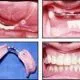

If a patient does not have enough tissue to support dentures, implants can be placed and an overdenture using a bar attachment can be made. An overdenture is much more stable than a conventional complete denture, so the patient can function better for chewing and speaking, and it is also more comfortable. If the patient has enough bone tissue to receive more implants, usually eight to ten per arch, it is possible to make all the fixed crown and bridge.